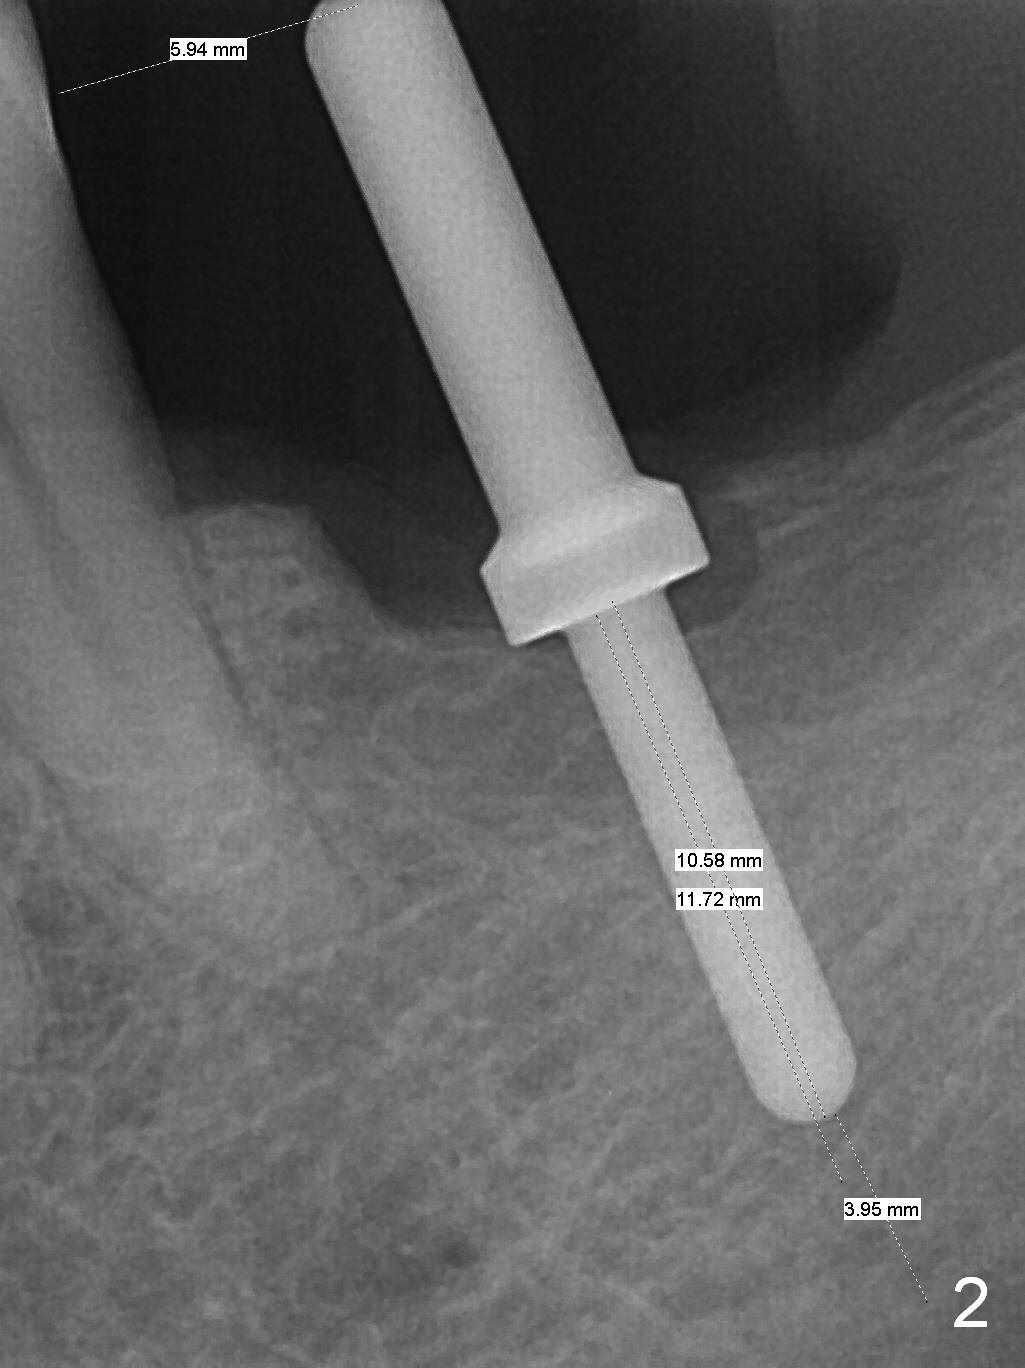

As indicated by CBCT, the ridge at the site of #19 is pointed (Fig.1). After regional ridge reduction (Fig.2) and use of 2 mm pilot drill for 8.5 mm, the depth is actually ~ 10 mm. After sequential osteotomy until 4.3x10 mm drill, the osteotomy is in fact 11.5 mm deep; a 5x11.5 mm implant is placed with <35 Ncm (Fig.3). Panoramic X-ray shows the implant close to the superior border of the Inferior Alveolar Canal (Fig.4 red dashed line). The ridge looks wider and more bulging (*) when a 6.5x5.5(5) mm abutment, allograft/Osteogen and Osteotape (GBR) are placed (Fig.5 (lingual) and 6 (buccal)). Periodontal dressing is then applied. There is no postop paresthesia. The abutment dislodges 3 weeks postop. A healing abutment is placed (6.5x4 mm). The patient returns for restoration 4 months postop; bone density appears to increase around the implant (Fig.7 arrowheads). When a 7.5x5(4) mm abutment is placed, there is transient pressure on the gingiva (blanching). The mesial gingival trough is formed by Diode laser prior to impression.